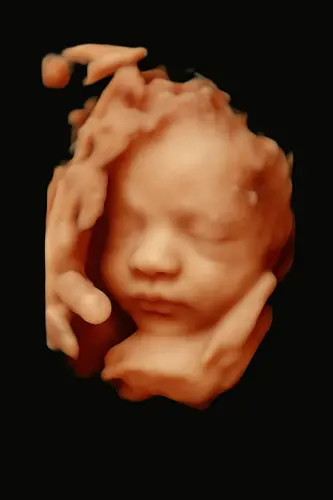

Ons menneke met 24 weken 💙

Wat een prachtig snoetje 😍